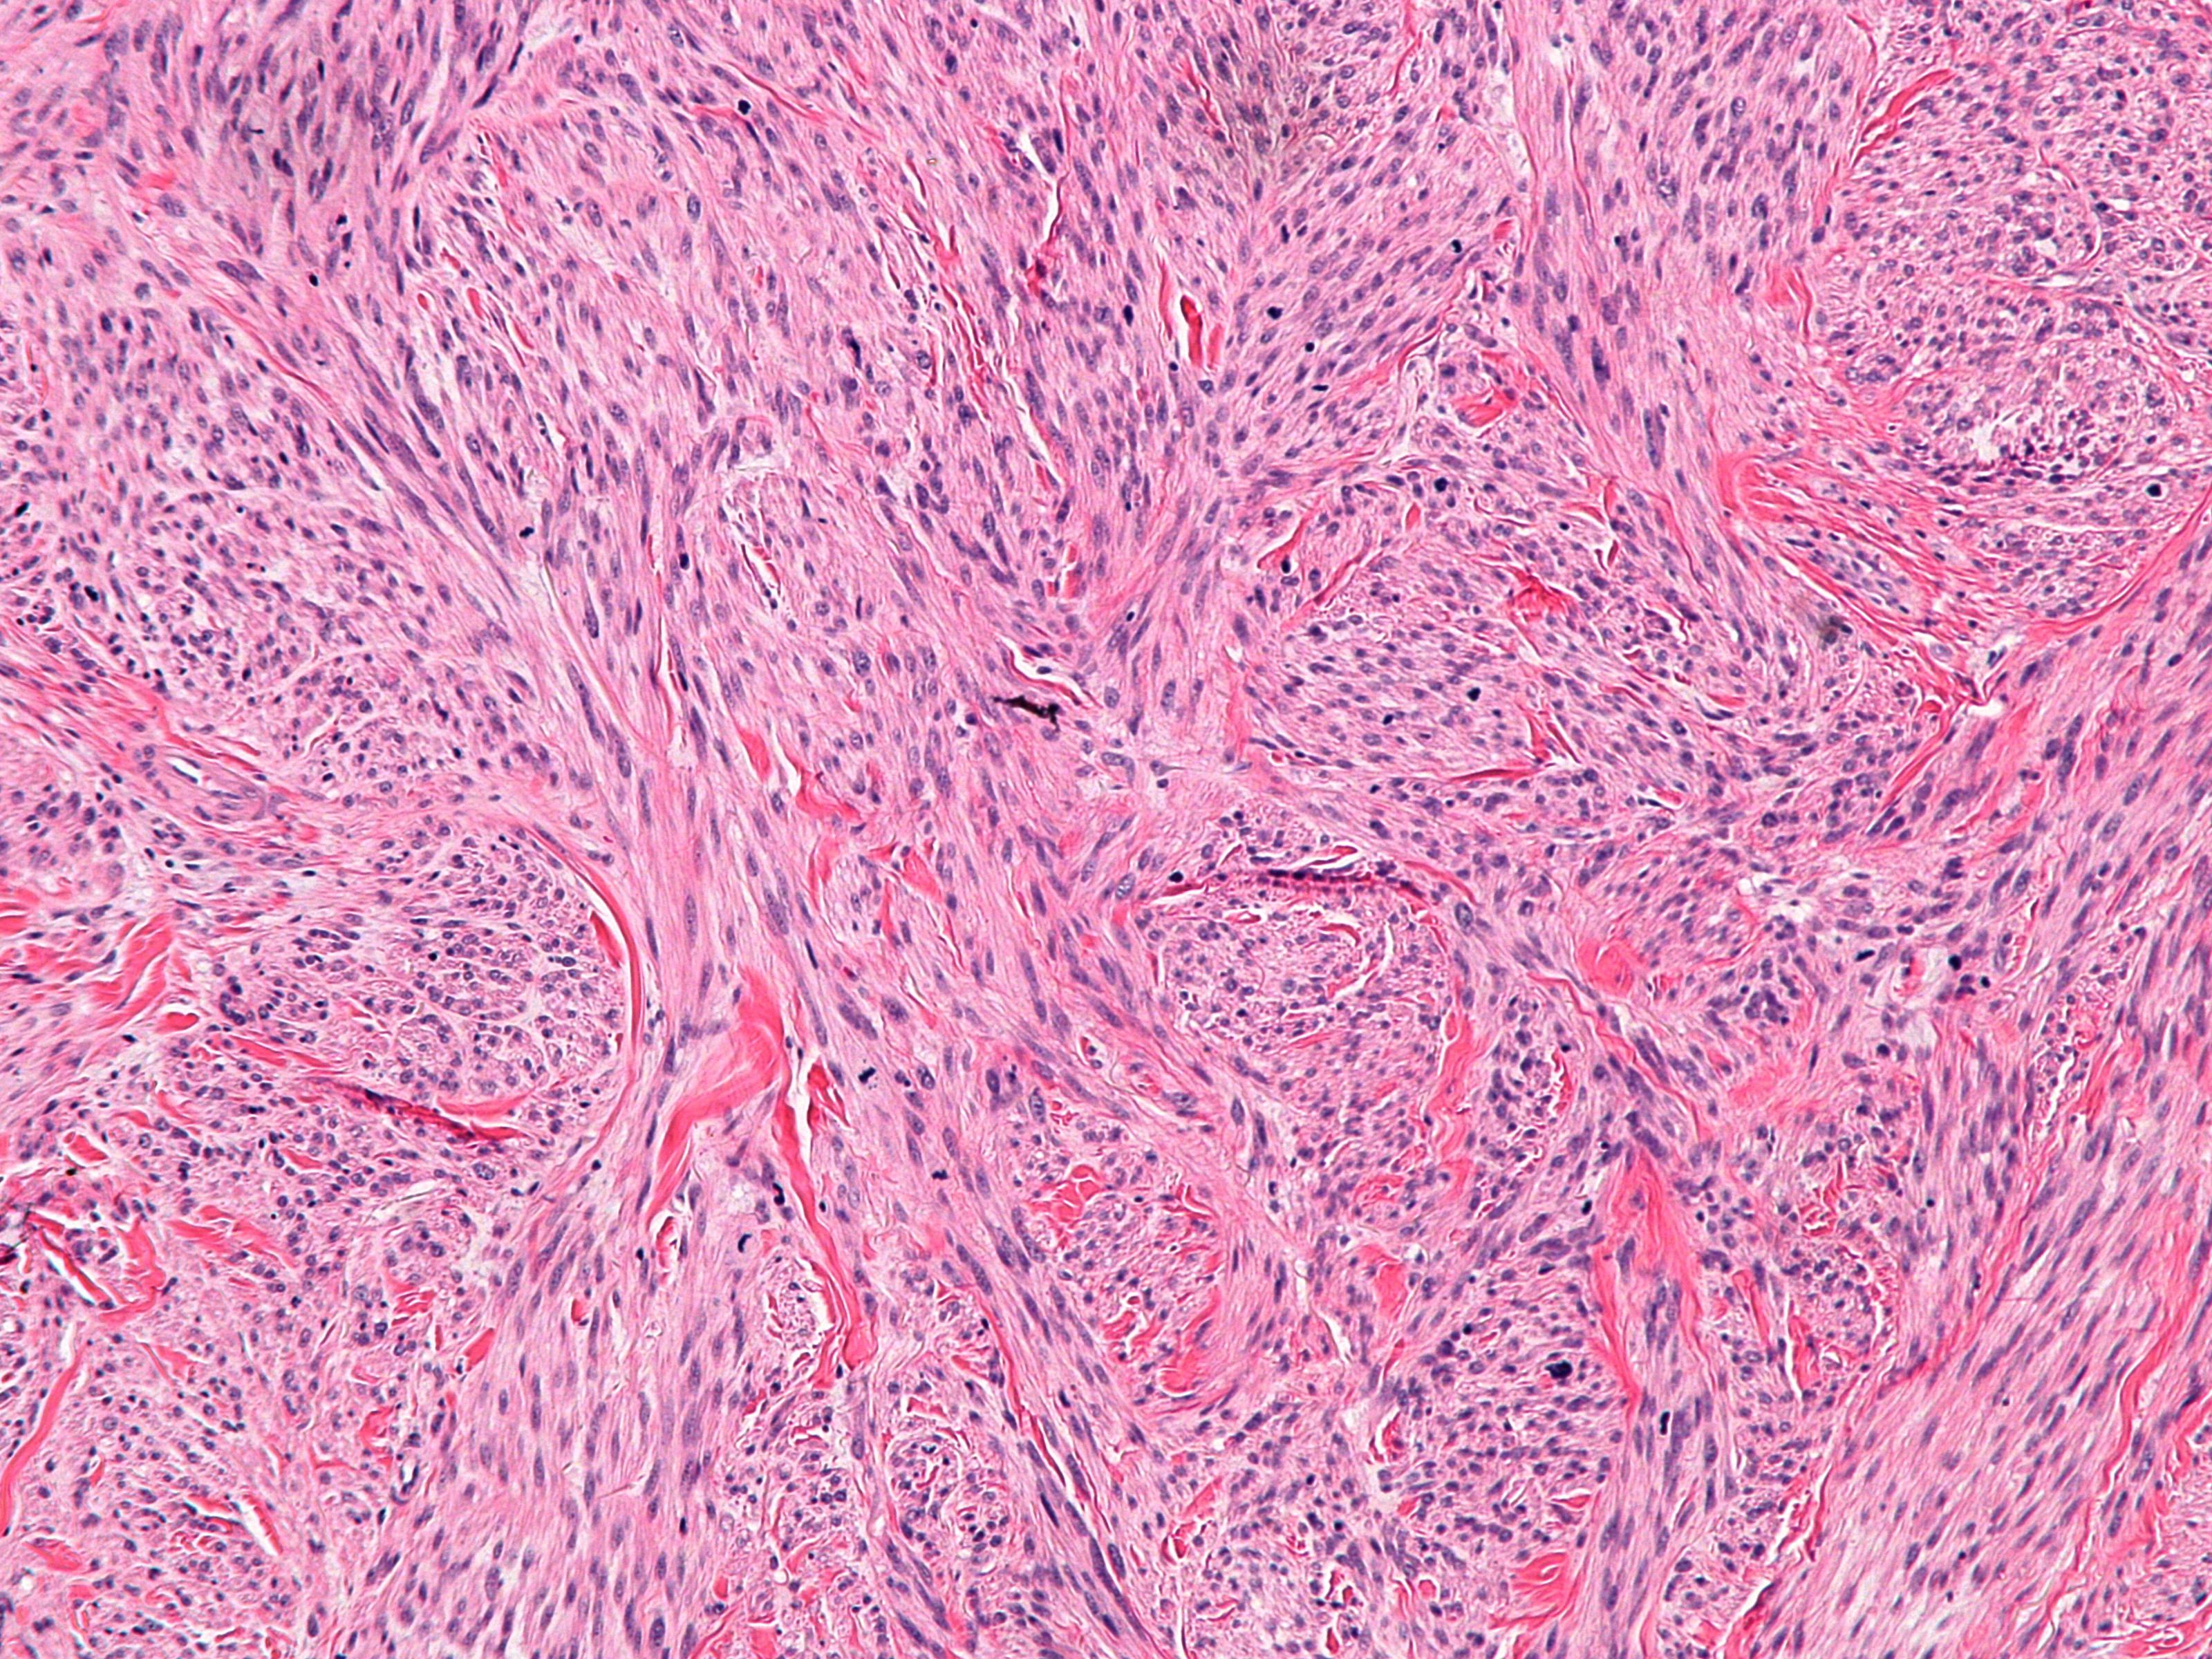

PA:Bij dermale leiomyosarcomen

zijn er slecht afgrensbare velden van tumorweefsel in de dermis en deels subcutis.

De subcutane leiomyosarcomen zijn beter afgrensbaar. De laesies zijn opgebouwd

uit bundels van glad spierweefsel. De cellen zijn spoelvormig, met langwerpige

kernen en een fibrillair eosinofiel cytoplasma. Soms heldere perinucleaire halo’s.

Er is nucleaire atypie en er zijn mitosen te zien. Het kan moeilijk zijn om

het onderscheid te maken met een benigne leiomyoom. Er bestaan zeldzame histopathologische

varianten (met epithelioid cellen, multinucleaire reuscellen, granular cells,

sclerotisch, pleomorf, myxoid). Immunohistochemie: goed gedifferentieerde leiomyosarcomen

kleuren aan met vimentine, desmine, h-caldesmon, muscle-specific actin, alpha-smooth

muscle actin, en smooth muscle myosin. Soms ook met S-100 en cytokeratinen.

Slecht gedifferentieerde zijn vaak negatief voor desmine. Andere spoelcellige

laesies zoals dermatofibrosarcoma protuberans, fibrosarcoma, nodulaire fasciitis,

desmoplastisch melanoom, spoelcellig carcinoma, spoelcellig atypisch fibroxanthoma,

malignant peripheral nerve sheath tumor, synoviaal sarcoma, en vasculaire tumoren

kunnen worden onderscheiden omdat deze aankleuren met EMA, CD34, CD117, CEA,

HMB45, Mart-1, Melan A of CK7, en leiomyosarcoma niet. Het onderscheid met een

benigne leiomyoom kan worden gemaakt met p53 (positief in leiomyosarcoma, niet

in leiomyoma).